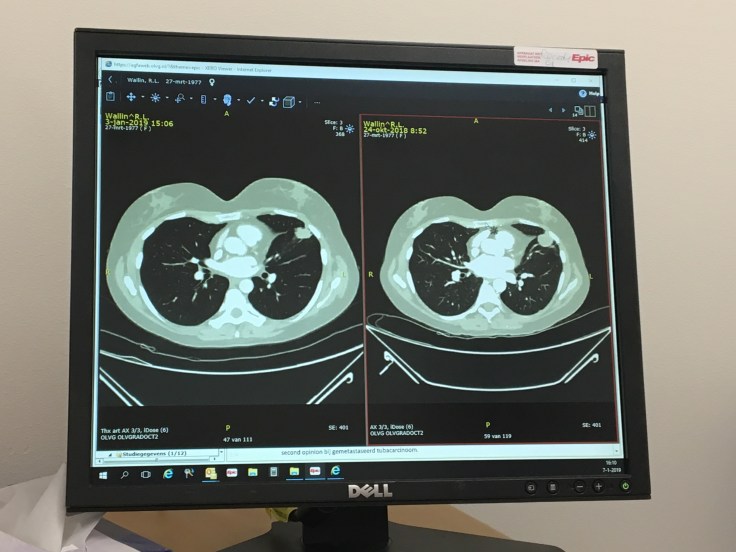

On January 3rd, I kicked off the new year with a CT scan. This was always in the plan; having already had localised / targeted treatment to take out the first tumour in my brain, then started chemo to attack the second tumour in my lung (and any other nasties which my be lurking undetected), the CT scan was a half way point in chemo to see if it was working, and four days later, I’d return to OLVG to see the lovely Dr Kerver for the results.

Yep, the good news is that CT scan showed a 17% reduction in size since 24th October (before chemo started). This not only means the second tumour has taken a beating, but any other cells which may be lurking undetected, will also have felt it. This doesn’t guarantee we’re killing everything, but Mutley’s army is getting smaller.